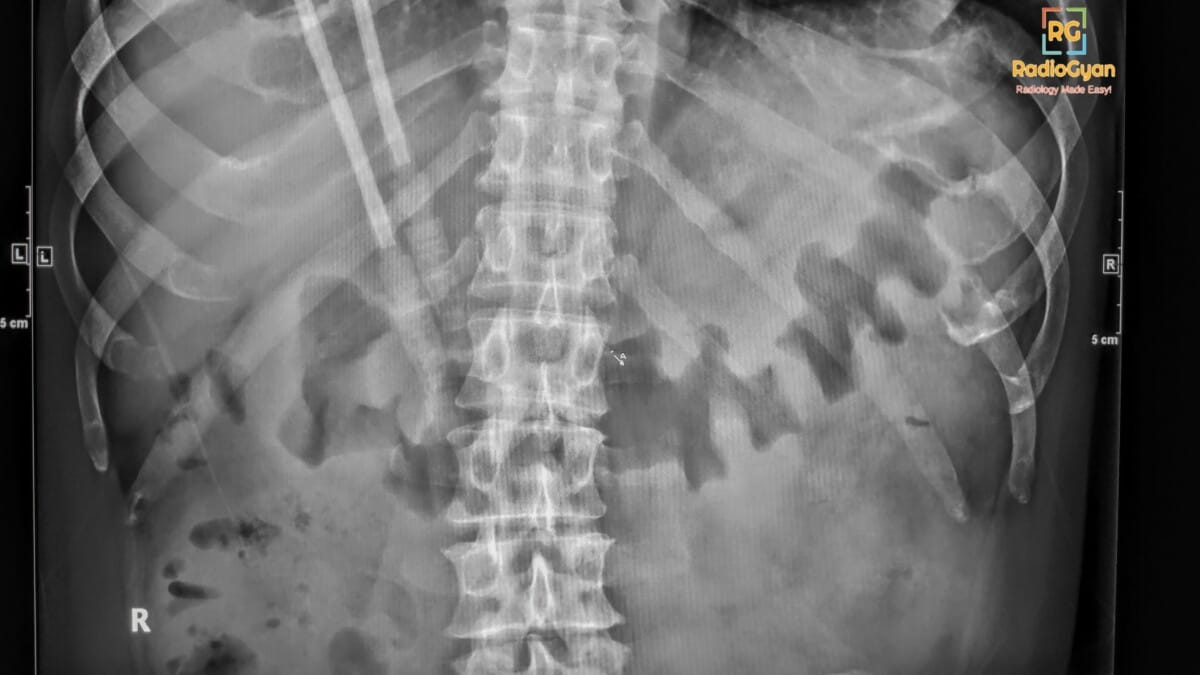

Thumbprinting in the large bowel on plain radiography is caused by thickening of the bowel wall, primarily due to submucosal edema that results from inflammation or ischemia. This radiologic sign of bowel wall edema is commonly associated with conditions such as ischemic colitis, infectious colitis (including pseudomembranous colitis), inflammatory bowel disease, and other causes of bowel wall edema like diverticulitis or hemorrhage.

It is called “thumbprinting” because the thickened, inflamed haustral folds project inward into the gas-filled bowel lumen on radiographs, resembling rounded impressions similar to thumbprints.

The pathological process involves edema and inflammation within the submucosa of the bowel wall, leading to localized swelling and thickening of the mucosal folds. This thickening creates nodular, thumb-shaped protrusions on imaging that indent the bowel lumen, giving the characteristic radiographic appearance known as thumbprinting. It reflects compromised bowel wall integrity often due to ischemia, infection, or inflammation.